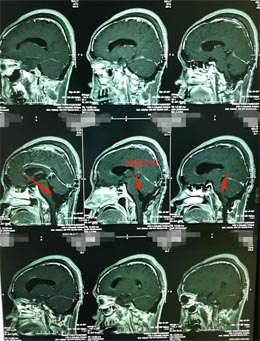

▲术前MR

肿瘤来源于四脑室底,与脑干关系密切。第四脑室是一个非常重要的解剖区域,腹侧毗邻桥脑、延髓等脑干结构,又是脑室系统内脑脊液循环通路的最后环节,由于瘤体周围有重要的神经、血管组织,故手术对肿瘤进行彻底切除难度较大。目前情况下,手术仍是首选的治疗方法。

室管膜瘤根据其恶性程度和侵袭性分为4级,从1至4级,恶性度逐级递增,因为此肿瘤多位于脑室内,有一定的生长空间,故疾病早期症状不明显,因此也很难做到早期发现。术中在高倍显微镜将肿瘤从脑干分离,手术难度、风险大,容易损伤脑干导致昏迷不醒,如果能尽可能的进行全部切除肿瘤,病人的生存时间会更长。本手术成功完全切除肿瘤,没有留下后遗症。